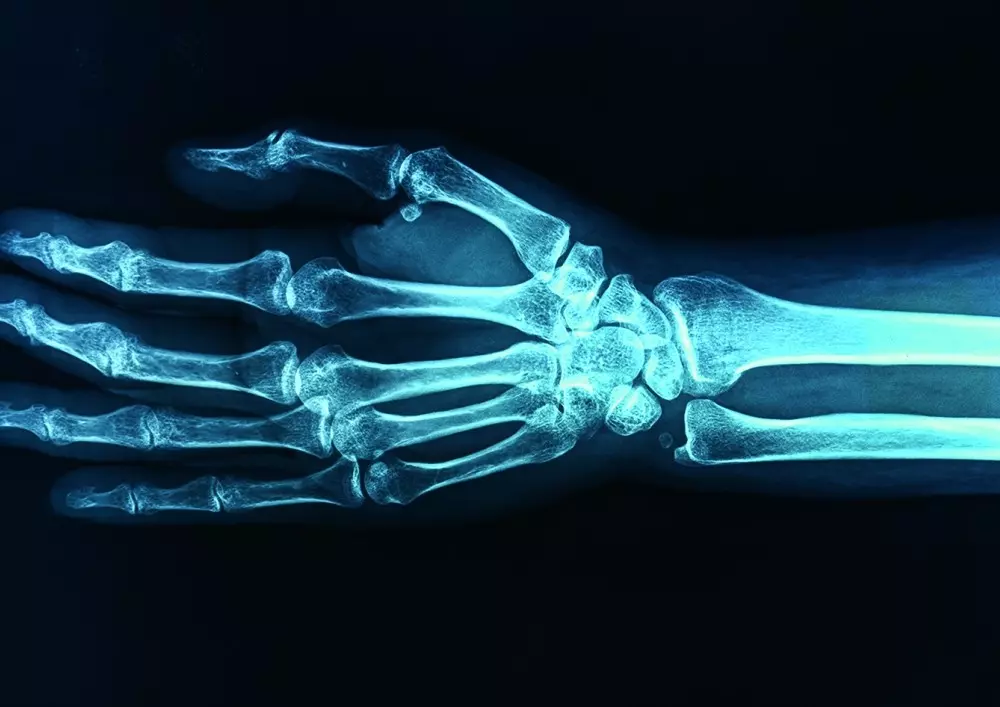

W dziale „Z praktyki gabinetu” publikujemy artykuł pt. „Postępowanie terapeutyczne w leczeniu zarostowego zapalenia stawu ramiennego”. Dr n. kf. Marcin Grześkowiak podkreśla ból i ograniczoną ruchomość stawu ramiennego, a także obniżenie możliwości funkcjonalnych wiążące się z tym schorzeniem. Zarostowe zapalenie stawu ramiennego wymaga fizjoterapii i terapii manualnej. Przedstawiamy przebieg choroby, objawy kliniczne, rozpoznanie, badanie funkcjonalne oraz planowanie terapii.